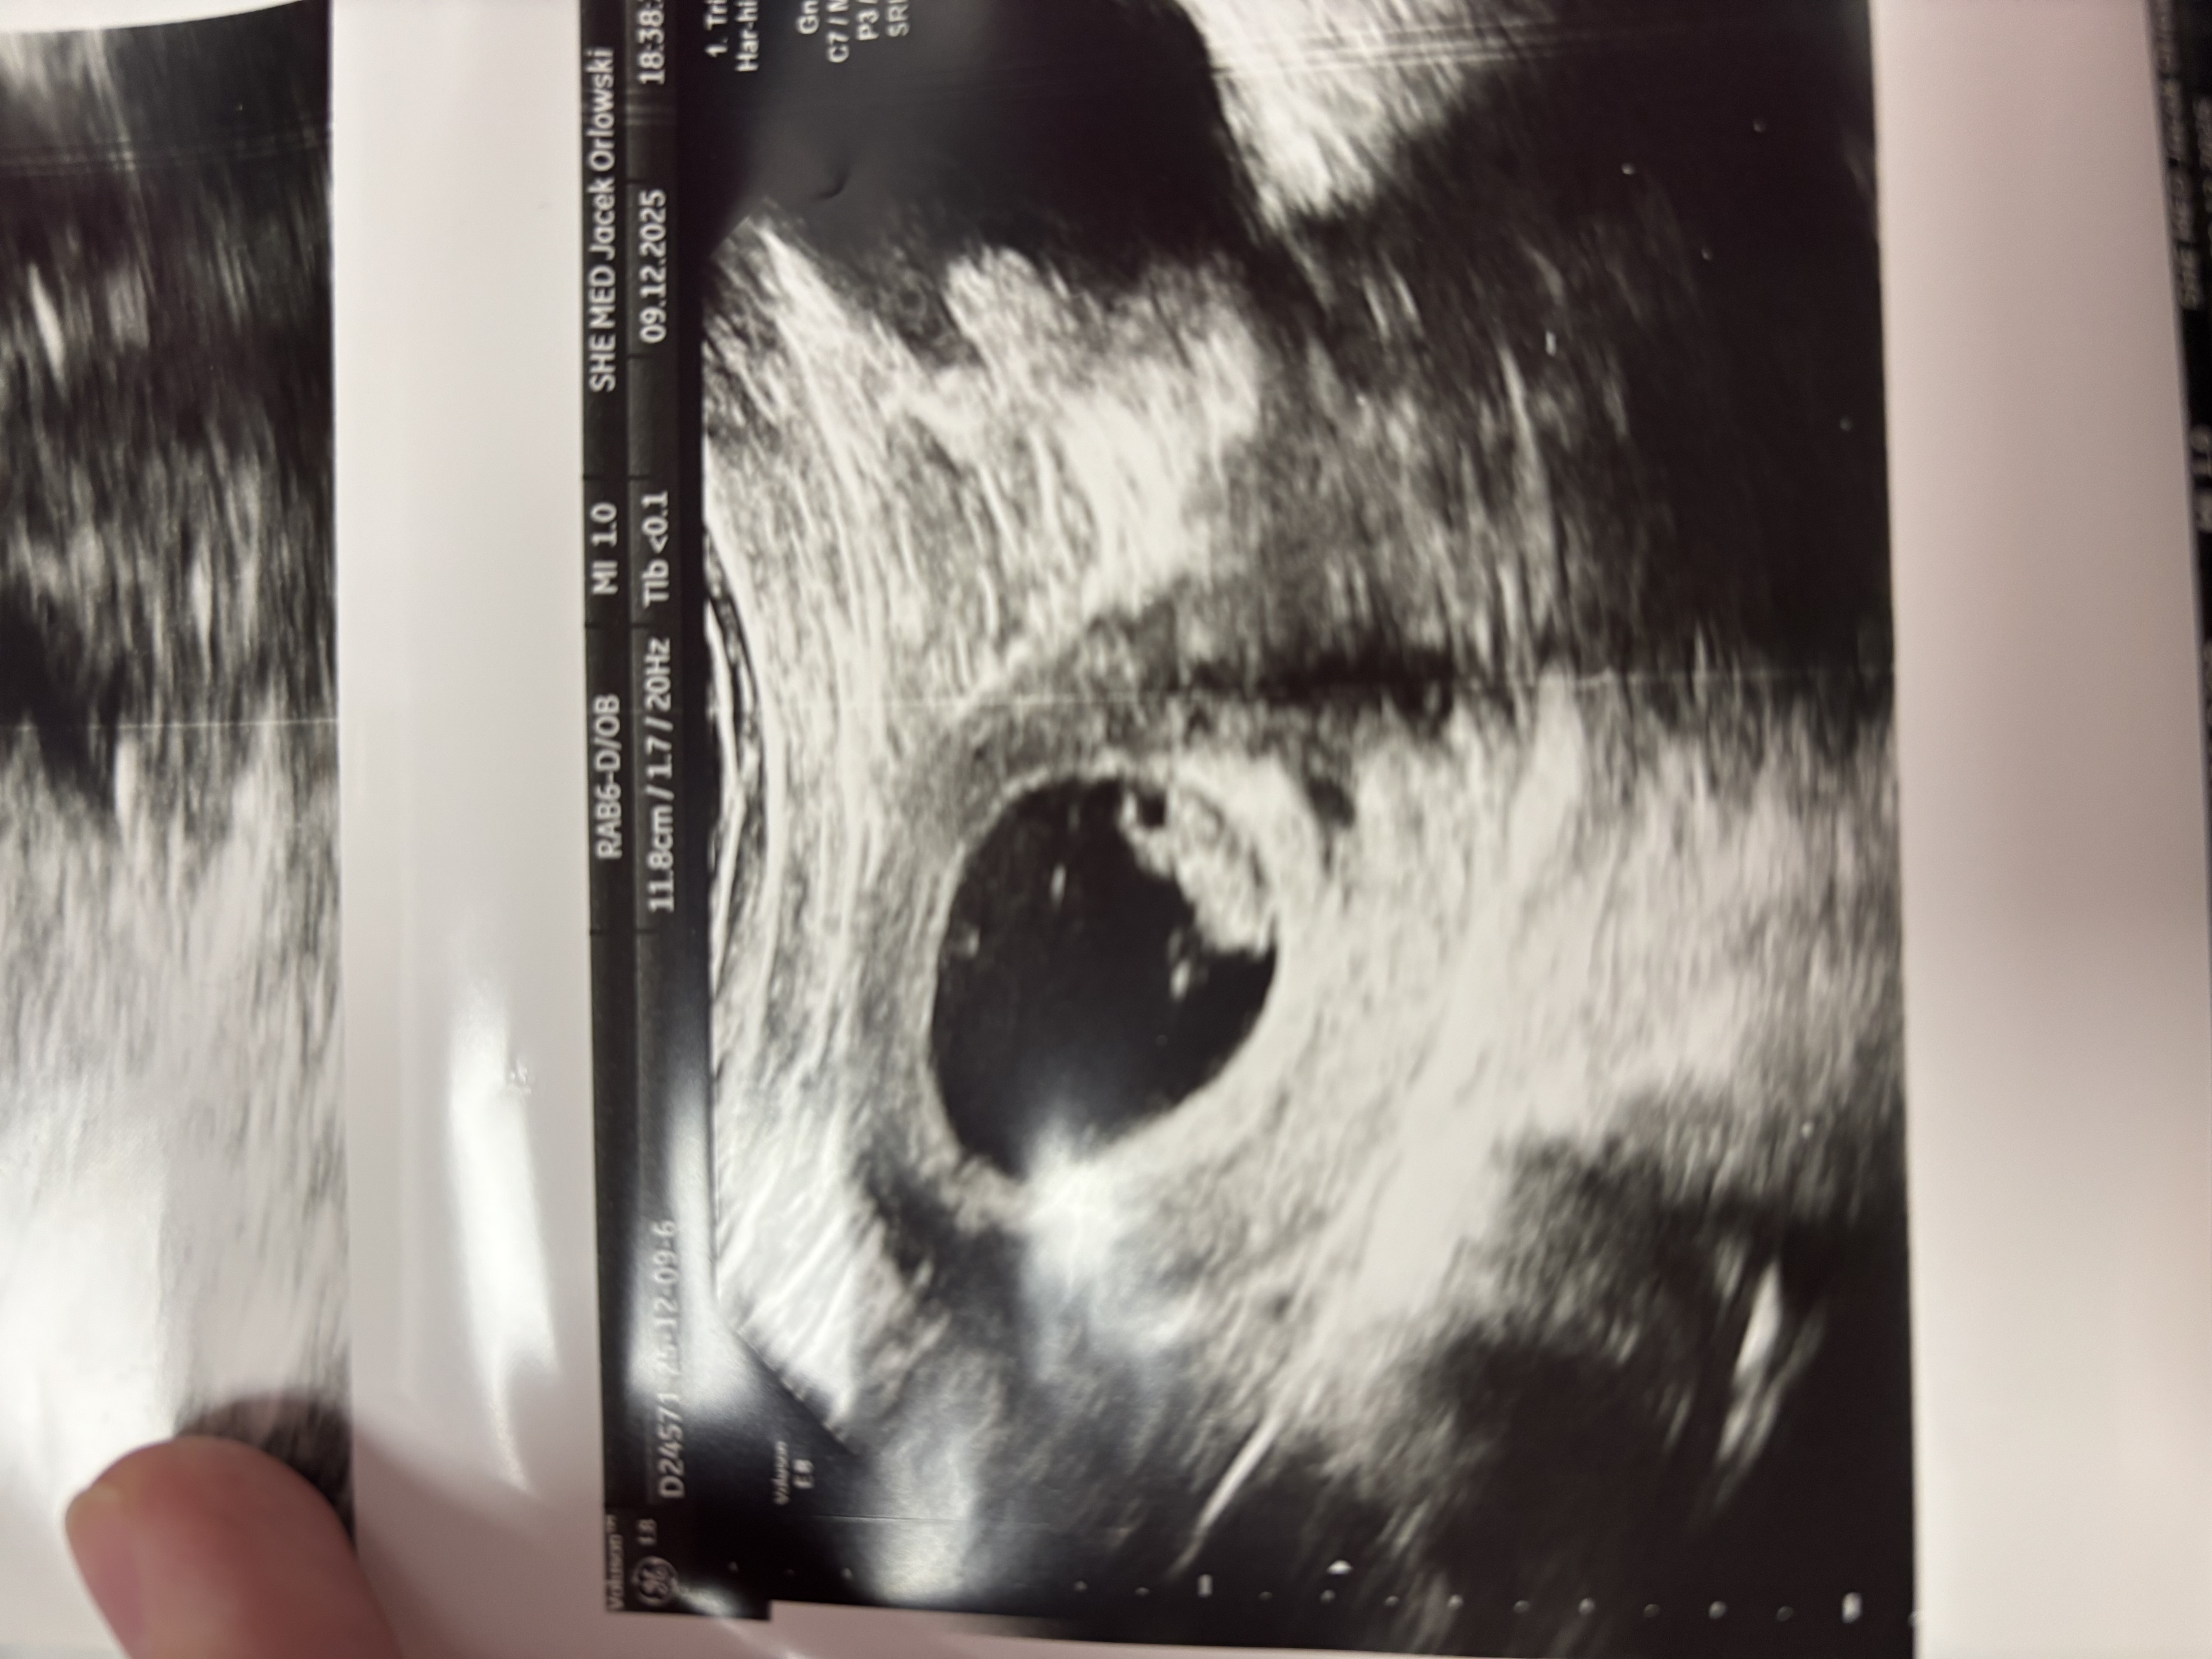

Ja po wizycie, 8+1 i wszystko w porządku. Ale potem prosto od lekarza pojechałam do sklepu i do apteki i panie w aptece musiały mnie cucić bo zasłabłam.

Nie mogę w ciąży stać w kolejkach ani robić większych zakupów bo zaraz mi się słabo robi. A że brzucha nie mam to ludzie nie przepuszczą w kolejce tylko się gapią… Zobacz załącznik 1730480

Dziewczyny u nas już po wizycie, to była pierwsza u ginekologa “normalnego” a nie w klinice IVF. Wszytsko wygląda ok, mamy 3,4cm małego człowieka ❤️❤️

Ja też jestem dziś 8+1, ale wizytę mam za tydzień w środę. Dzidziuś już duży🤩